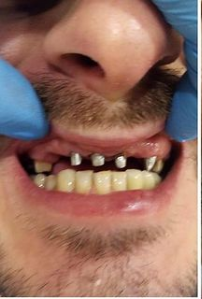

Установка металлокерамической коронки

Доктор: Базаян Арсен Андреевич